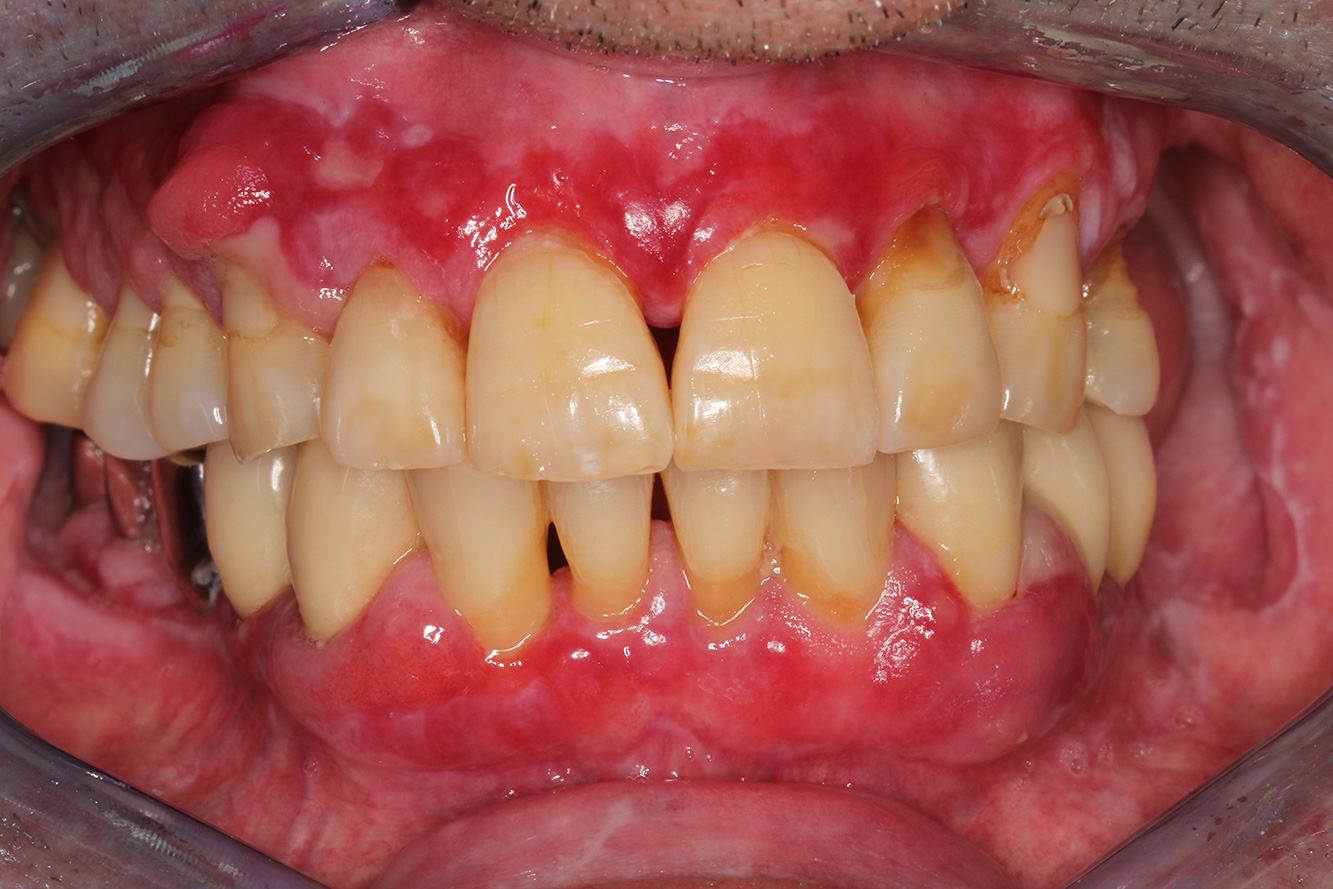

NIWOP – No Implantology without PeriodontologyDer Transplantationspatient mit GingivawucherungenEin 71-jähriger Patient mit Z.n. Nierentransplantation und Hypertonie (Bluthochdruck) stellt sich vor. Bedingt durch die Krankengeschichte ist eine Dauermedikation mit Cyclosporin, zur Unterdrückung der Immunabwehr, und Amlodipin, zur Blutdrucksenkung, erforderlich. Außerdem berichtet der Patient über empfindliches Zahnfleisch und Zahnfleischbluten. Aus mundgesundheitlicher Sicht zeigt sich ein saniertes Gebiss mit acht fehlenden Zähnen, ausgeprägte Gingivawucherungen, eine Parodontitis Stadium II, Grad B mit aktiven Taschen und eine initiale Wurzelkaries an Zahn 22. In der Kariesrisikoabschätzung wird ein mittleres Kariesrisiko (API 60) festgestellt. Für die Prophylaxesitzung lassen sich folgende Behandlungsempfehlungen ableiten. mehr Infos * mit freundlicher Genehmigung von Dr. G. Schmalz und Prof. Dr. D. Ziebolz MSc. Download AreaProxeo Produkte